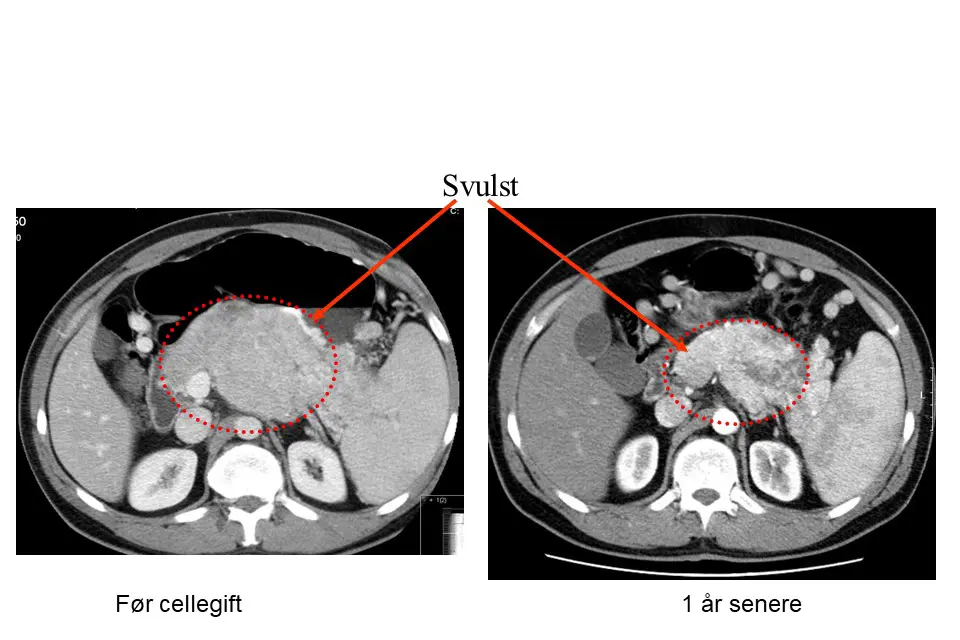

Foto: Oslo universitetssykehus

To bilder som viser nevroendokrin svulst i bukspyttkjertelen hvor man kan se reduksjon av svulsten etter 1 år med cellegift